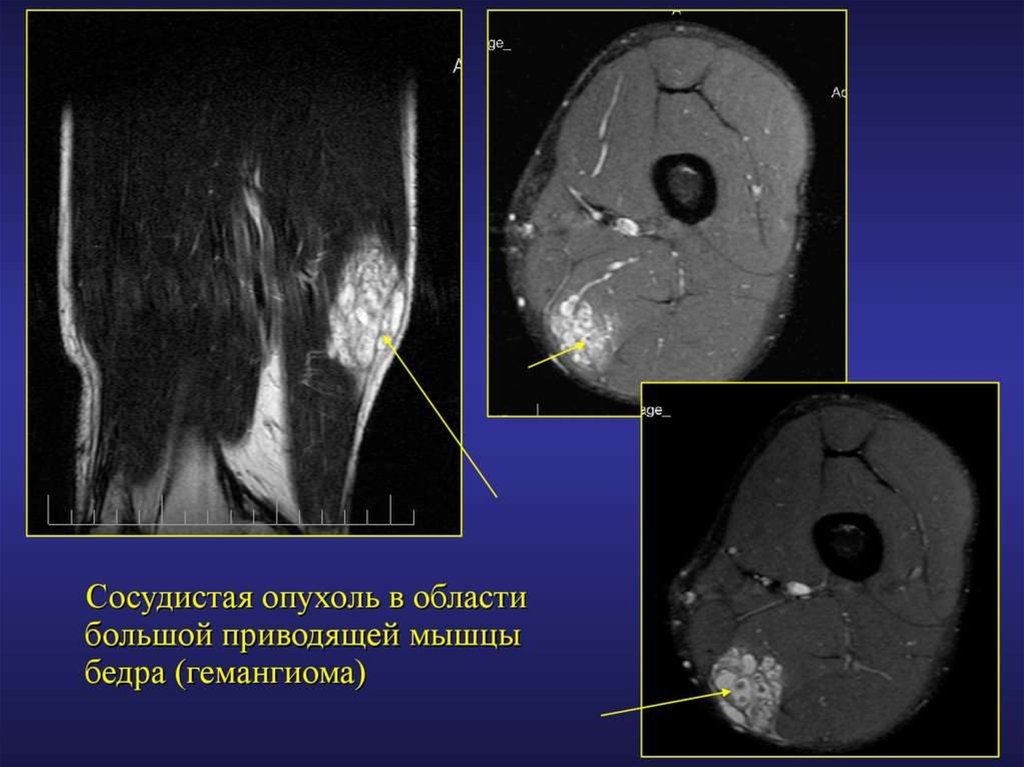

МРТ диагностика повреждений и заболеваний мягких тканей